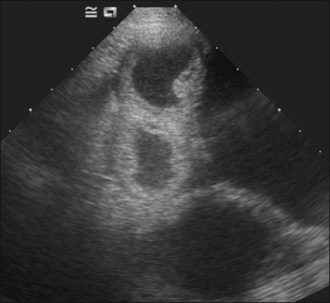

Abdominal radiography reveals convoluted loops of tubular fluid opacity in the caudal abdomen with dorsal displacement of the descending colon (Figure 29.9), and ultrasonography shows enlarged uterine horns distended with hypoechoic fluid (Figure 29.10).

Figure 29.10 Ultrasonographic appearance of pyometra. Enlarged uterine horns distended with hypoechoic fluid are visible in proximity to the urinary bladder.